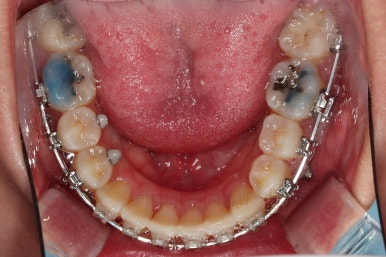

치열만 보면 매우 가지런해진 것 같죠?

이때가 대략 8개월 정도 지났을 때의 모습인데요.

어차피 비대칭은 수용해야 되고, 중앙서노 100% 안맞으니 이정도만 해도 매우 양호한 것 같죠?

하지만 해볼만한 치료는 상당히 많습니다.

여전히 돌출감이 있기 때문에 전 치열을 후방이동해서 입매를 개선해 주고요.

앞에서 봤을 때 치열은 가지런해졌지만 기울어진 느낌을 조금이라도 잡아보고자 미니스크류를 이용해서 입매 개선 및 기울기 개선을 시도했습니다.